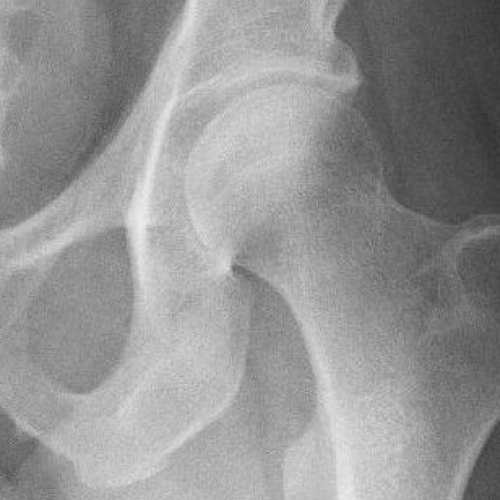

LECZENIE KONFLIKTU UDOWO-PANEWKOWEGO (FAI – femoroacetabular impingrment)

Dotyka najczęściej młodych aktywnych fizycznie osób, które przez dolegliwości bólowe w stawie biodrowym nie są w stanie aktywnie uprawiać sportu, W Ortho Sport Clinic stosujemy metodę leczenia z wykorzystaniem miniartrotomii do stawu biodrowego co skraca czas zabiegu, redukuje ilość wykorzystywanego promieniowania X podczas operacji oraz zapewnia doskonały wgląd do stawu biodrowego w razie potrzeby przeprowadzenia dodatkowej procedury np. rekonstrukcji obrąbka st. biodrowego.

Przed przystąpieniem do zabiegu konieczna jest konsultacja z jednym z naszych lekarzy, który zbierze ogólny wywiad, oceni stan ogólny kliniczny pacjenta, zleci wykonanie RTG i MRI stawów biodrowych oraz innych badań niezbędnych do kwalifikacji. Pacjent nie wymaga specjalnego przygotowania do tego typu zabiegu.